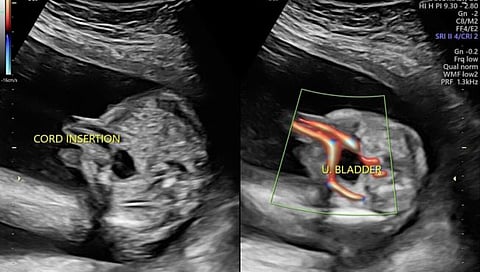

गर्भधारणेच्या वेगवेगळया टप्प्यांमध्ये बाळाचा विकास पाहण्यासाठी सोनोग्राफी केली जाते. त्यामध्ये एनटी स्कॅन आणि अॅनॉमली स्कॅनला विशेष महत्त्व असते. गर्भवतींच्या नेहमीच्या तपासणीमध्ये या दोन्ही स्कॅनचा समावेश असतो. झिकाच्या पार्श्वभूमीवर अॅनॉमली स्कॅनला विशेष महत्व आहे.

मात्र, महापालिकेच्या केवळ कमला नेहरु रुग्णालयामध्ये अॅनॉमली स्कॅनची सुविधा उपलब्ध आहे. यामध्ये एक मशिन महापालिकेतर्फे, तर एक क्रस्ना डायग्नोस्टिकतर्फे चालवले जाते. खासगी रुग्णालयांमध्ये अॅनॉमली स्कॅनसाठी अडीच हजार रुपये तर एनटी स्कॅनसाठी दीड हजार रुपये खर्च येतो. महापालिकेतर्फे शहरात १९ प्रसूतिगृहे चालवली जातात.